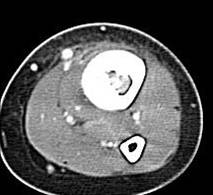

左胫骨中下段见一不规则虫蚀样骨破坏,走形方向与胫骨长轴一致,边缘轻度硬化,伴明显骨膜增生,ct见破坏区内见磨玻璃样密度,其旁软组织钟胀,内见不规则钙化。

左胫骨中下段见一不规则虫蚀样骨破坏,走形方向与胫骨长轴一致,边缘轻度硬化,伴明显规则的骨膜增生,ct见破坏区内见磨玻璃样密度,其旁软组织钟胀,内见不规则钙化。

病史资料不完善,根据年龄、部位、及影像学表现,主要表现胫骨骨干囊性骨质破坏,骨皮质受累,局部骨膜反应,未见骨膜破坏及瘤骨,未见放射状骨针。 首先要考虑胫骨转移瘤,建议进一步检查,除外视网膜母细胞瘤,神经母细胞瘤,肾母细胞瘤,肾上腺等恶性肿瘤骨转移。排除转移瘤后考虑嗜酸性肉芽肿可能性大,患者年龄5岁,尤文氏瘤不太考虑,骨肉瘤也不太符合,骨髓炎待排,影像表现不太支持。建议进一步检查,除外原发恶性肿瘤胫骨转移后,考虑嗜酸性肉芽肿。必要时穿刺活检。